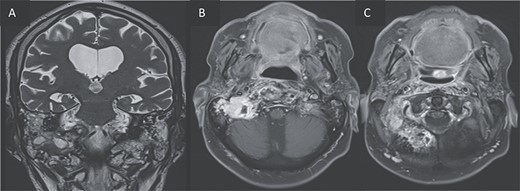

Furthermore, inflammatory changes were noted to extend into the petrous, tympanic, and mastoid segments of the right temporal bone, as well as involving the petrous and mastoid regions of the left temporal bone and the occipital bone. Additionally, small abscess cavities were observed within the right occipital condyle.

T2 coronal (A) and T1 post gadolinium axial images (B, C) showing the extension of the inflammation around the clivus and in the petrous, tympanic, and mastoid portions of the right temporal bone with small abscesses along the mastoid cells and the occipital bone.